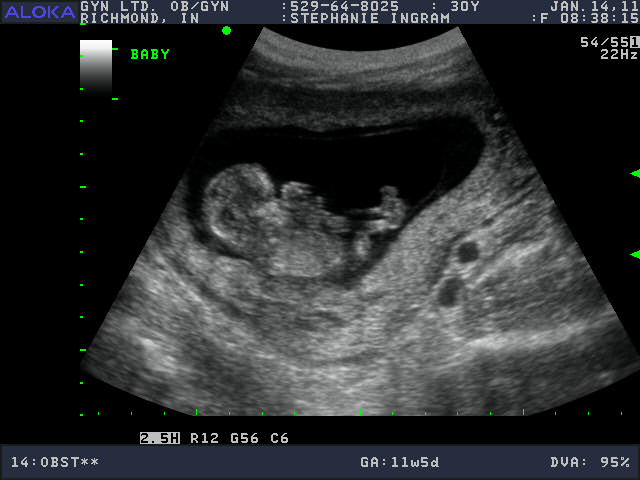

Cute Baby! 12 weeks along